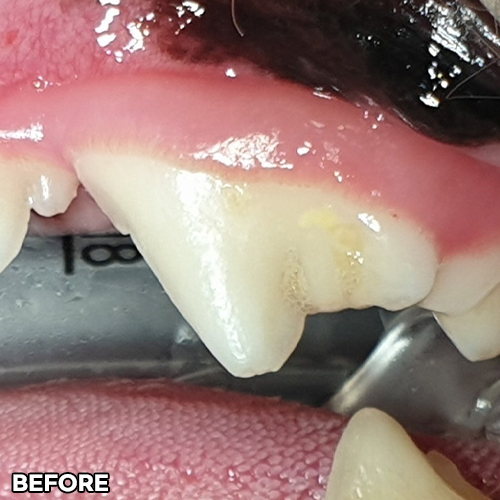

[대형견 마라노이즈 송곳니 레진치료 - 강아지치과 법랑질 저형성증 -]

[구멍난 강아지 치아 레진치료 전후]

[깨진 강아지 치아 레진치료 전후]

[강아지앞니 치료]

[강아지 치아의 구멍 레진치료 후 2주 경과]

[15년 노령견의 어금니 레진치료]